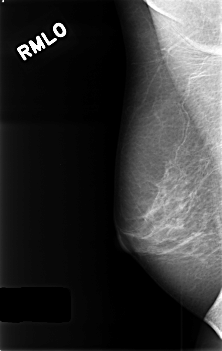

C_0406_1.RIGHT_MLO

RIGHT_CC LINES 4528 PIXELS_PER_LINE 2928 BITS_PER_PIXEL 12 RESOLUTION 50 NON_OVERLAY

RIGHT_MLO LINES 4560 PIXELS_PER_LINE 2880 BITS_PER_PIXEL 12 RESOLUTION 50 NON_OVERLAY